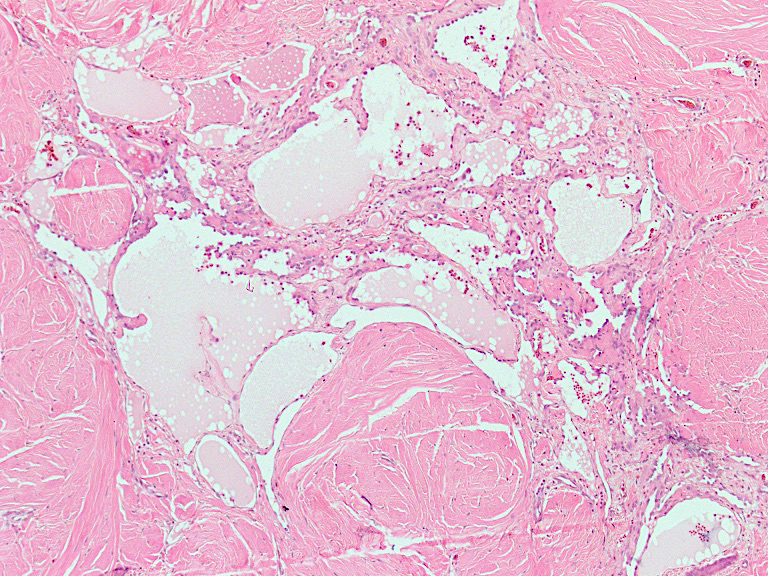

Microscopic (histologic) description

- Poorly circumscribed lesion, infiltrating dermis and subcutis with dissecting planes (Int J Clin Exp Pathol 2010;3:528)

- Composed of elongated arborizing vascular channels that resemble rete testis, hence the name

- Occasional solid growth may be seen (Stockman: Diagnostic Pathology - Vascular, 1st Edition, 2015)

- In the dermis, vessels may become ectatic and lose retiform appearance

Microscopic (histologic) images